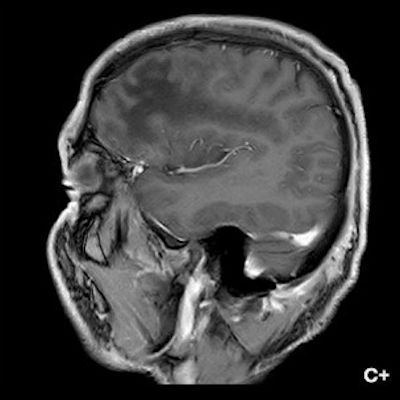

1. A) Aksiyel T2A görüntülerde bilateral sağda belirgin frontoparietal subkortikal ve derin periventriküler beyaz cevherde subkortikal U fiberleri boyunca yerleşimli sinyal artımları (oklar) izlendi.  Tarifli alanlar aksiyel T1A serilerde hipointens görünümde (oklar) izlendi.

2. B) Aksiyel diffüzyon ağırlıklı serilerde bilateral sağda belirgin frontoparietal subkortikal ve derin periventriküler beyaz cevherde periferal DAG hiperintens ADC hipointens, hafif diffüzyon kısıtlaması (oklar) eşlik etmektedir. IVKM sonrası kesitlerde tarifli alanlarda belirgin kontrast tutulumu (oklar) izlenmedi.

1. PML’de MRG bulguları genellikle multifokal, asimetrik periventriküler ve subkortikal beyaz cevher tutulumu şeklindedir. Subkortikal U-fiberleri sıklıkla tutulur, özellikle parietooksipital bölgelerde belirgin lezyon eğilimi vardır.

2. T1 ağırlıklı görüntülerde tutulan bölgeler hipointens, T2A’da ise hiperintens izlenir. Ana lezyon çevresinde çok sayıda noktasal (milkyway) sinyal artımları görülebilir. Ayrıca spleniumu çaprazlayan parietooksipital sinyal değişiklikleri (barbell bulgusu) ve dentat nukleusu koruyarak serebellar beyaz cevher tutulumu (shrimp bulgusu) da tanımlanmıştır.

3. Kontrastlı incelemelerde genellikle kontrast tutulumu izlenmez. Diffüzyon görüntülemede özellikle lezyonun ilerleyen periferik alanlarında yamalar halinde diffüzyon kısıtlılığı izlenir. MR spektroskopide NAA azalması, laktat varlığı ve artmış kolin ve lipid düzeyleri görülür. MR perfüzyonda ise lezyonların ilerleyen kenarında perfüzyon artışı saptanabilir.

4. Bizim hastamızda bilinen HIV enfeksiyonu mevcuttu ve yapılan kraniyal MR görüntülemede multifokal, asimetrik, periventriküler ve subkortikal beyaz cevherde yerleşimli, kitle etkisi göstermeyen ve kontrastlanmayan lezyonlar izlendi. Lezyonların subkortikal U-fiberleri tutması ve özellikle parieto-oksipital bölgelerde belirgin olması nedeniyle ön planda PML düşünüldü. Histopatolojik tetkik ile PML tanısı doğrulandı.